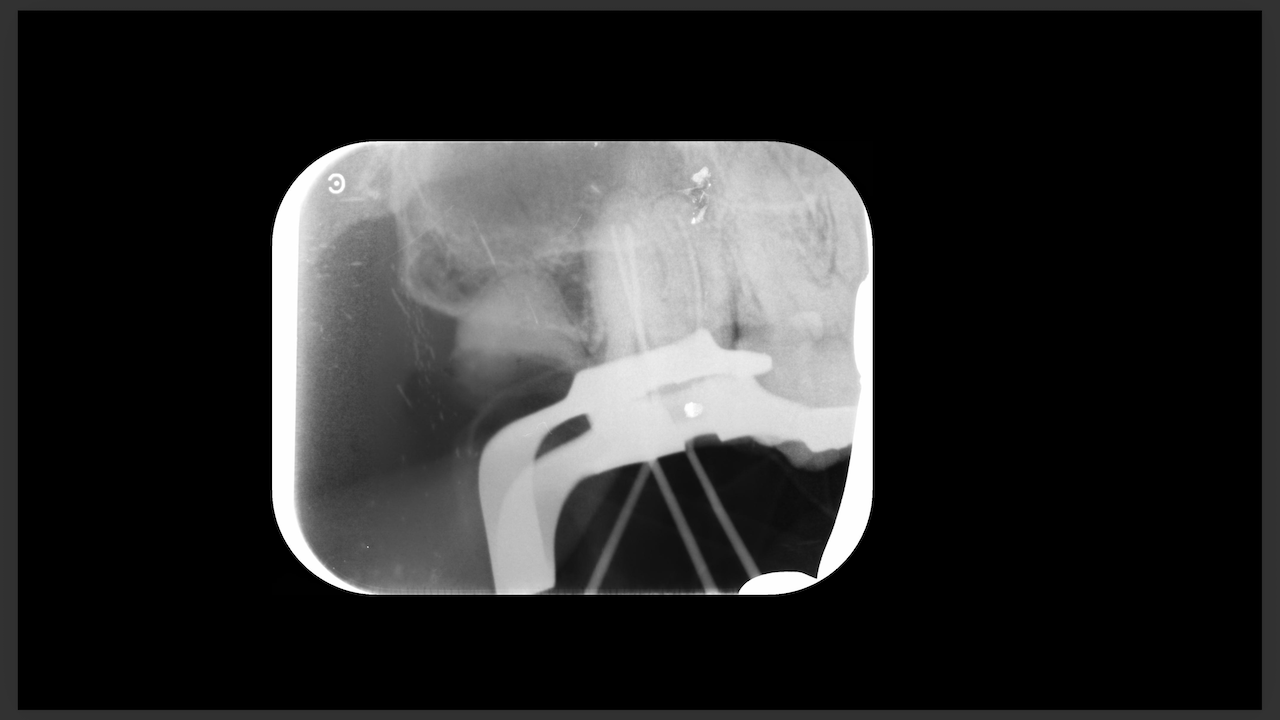

術前にCBCTを撮影したので、MB2がないということを分かった上で根管治療を行っている。

これがCBCTを歯内療法に用いる最大の利点だろう。

上手い!